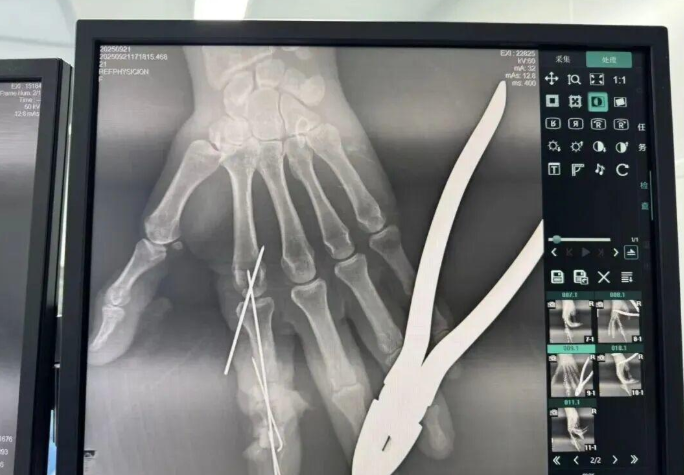

為確保手術(shù)成功,楊志主任特別聯(lián)合劉金海主任組成多手術(shù)組協(xié)作團(tuán)隊(duì),充分發(fā)揮梯隊(duì)配合優(yōu)勢,反復(fù)研討后確定了“組合式”手指再造方案:利用右足踇趾的皮瓣、末節(jié)甲床及部分趾骨,聯(lián)合第二趾的趾間關(guān)節(jié),再取部分髂骨進(jìn)行精確植骨,將這些組織精密拼裝,重建一個(gè)兼具良好外形和功能的新示指。

手術(shù)當(dāng)天,多手術(shù)組梯隊(duì)配合的優(yōu)勢得到充分體現(xiàn)。無影燈下,楊志主任與團(tuán)隊(duì)各司其職、緊密配合,一場漫長的生命接力就此展開。在放大40倍的專業(yè)手術(shù)顯微鏡下,醫(yī)生們開始了精細(xì)操作。楊志主任在術(shù)后解釋道:“患者需要吻合的血管直徑僅0.5-1.0毫米左右,末節(jié)手指的毛細(xì)血管更是細(xì)如發(fā)絲。我們必須將移植組織與手部的血管、神經(jīng)、肌腱進(jìn)行精準(zhǔn)吻合,確保移植組織通血成活。這不僅要求醫(yī)生有扎實(shí)的顯微外科技術(shù),還要具備專業(yè)的整形外科審美能力,才能讓再造的指尖既好用又好看?!?/p>